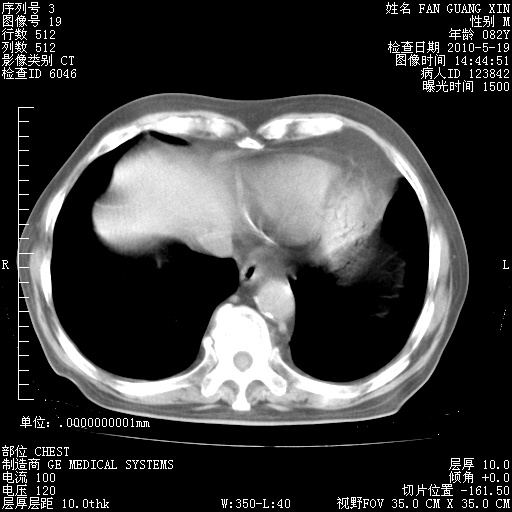

复查肺部CT,明显好转。为什么发热呢?

治疗3周后的肺部CT

治疗3周后的肺部CT纵隔窗